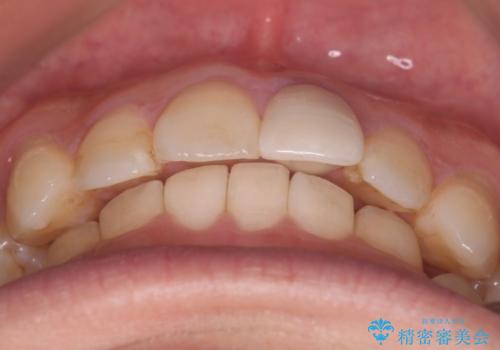

- 前歯のがたつきと口元を下げたいとのことで来院されました。

骨格的に左右差があるので正中を合わせることと抜歯矯正での口元改善は難しいことを説明させていただきました。

患者様に理解していただいた上で、インビザラインにてIPR(歯と歯の間を削る処置)を行いながら前歯のがたつきを整える治療計画を立てました。

インビザラインにて治療を行うことで、前歯のがたつきが改善されました。

左上1番目の前歯はセラミックをご希望されたので、セラミックにて被せ物の治療を行いました。

とても綺麗な前歯になりました。